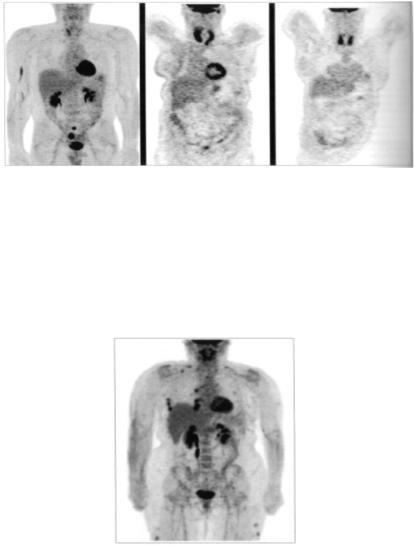

А

В

С

Рис. 7. Активность ФДГ в щитовидной железе может сильно отличаться: от нормальной - испещренная картина (А), ассиметричное накопление активности, связанное с мультицентричным зобом от хронического аутоиммунного тироидита (В), очень симметричное накопление, связанное с лимфомой с поражением щитовидной железы (С).